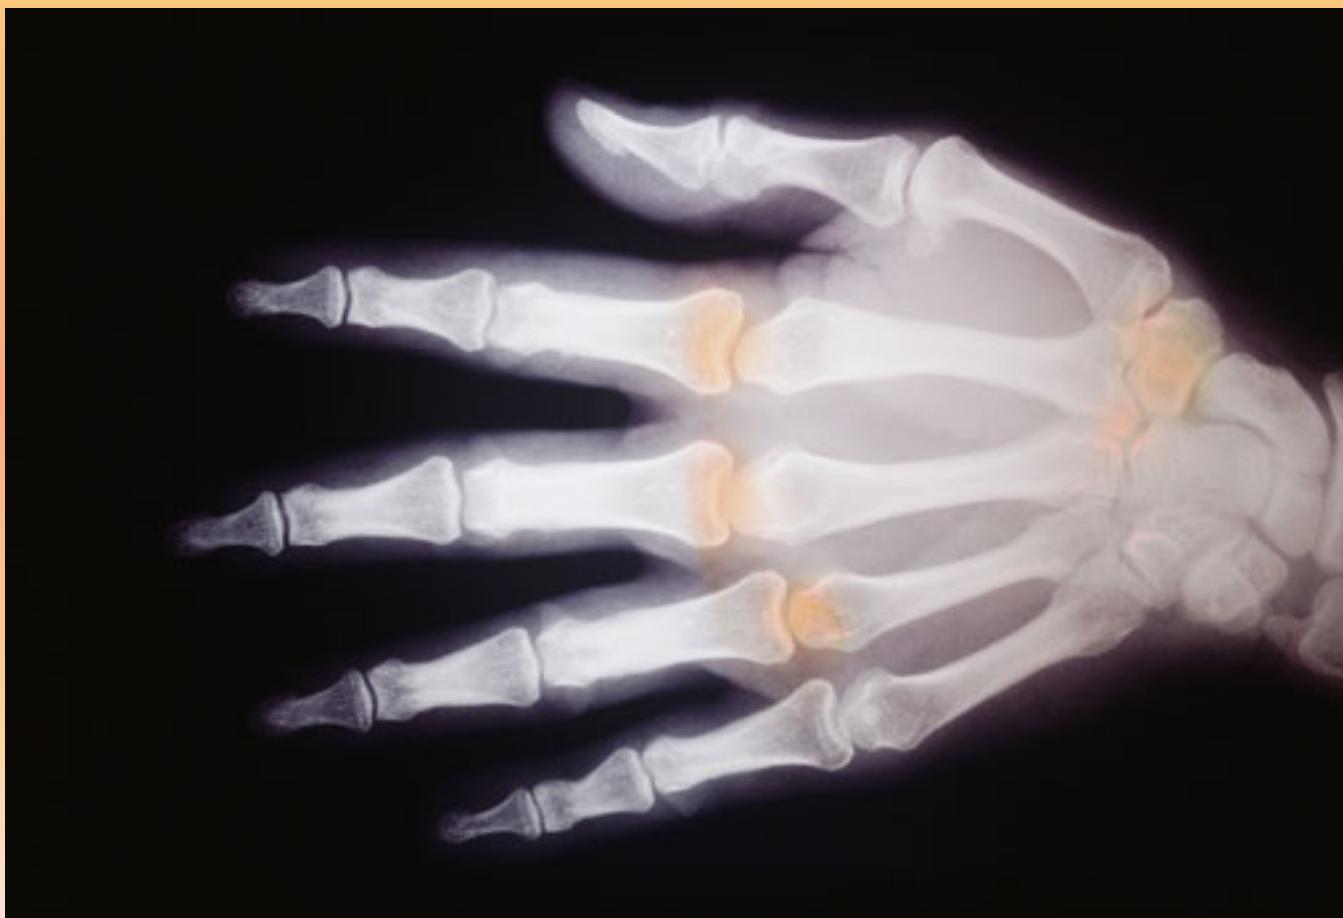

- Hand Joints (Below 18 years):

- Distal ends of metacarpals not united with shafts

- Proximal ends of phalanges not united

- Above 18: All hand bones united (